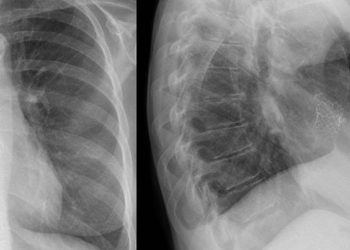

Strictures occur in an estimated 15-30% of Crohn’s Disease (CD) patients within the first 10 years after diagnosis. Several methods have been developed for evaluating small-bowel strictures, including computed tomography enterography (CTE) and double-balloon enteroscopy (DBE). CTE is very effective at detecting small-bowel disease, with a sensitivity and specificity of 83% and 88% respectively. Meanwhile, DBE has the benefit of allowing direct visualization while obtaining biopsies for histopathologic analysis. However, the relationship between symptom severity and the strictures detected through DBE is unknown. Therefore, this prospective cohort study aimed to determine the detection rate of DBE for CD patients with small-bowel symptomatic strictures. The study participants were enrolled from a single centre in China. All received both CTE and DBE, within one month of each other. The symptom severity was assessed through the Crohn’s Disease Obstructive Score (CDOS), with patients divided into low severity (scores 1-3) and high severity (scores 4-6). In total, there were 165 CD patients included, 42.4% of whom had low severity symptoms. The study found that detection rates of 92.7% and 85.5% through DBE and CTE respectively. For DBE, the rates were 91.4% and 94.7% in the low severity and high severity groups respectively (p = 0.13), whereas for CTE, the detection rate was greater in the high severity than the low severity group (90.1% and 75.9% respectively, p = 0.01). Overall, this study demonstrated that DBE is a very effective method for diagnosing small-bowel strictures in CD patients, with no difference depending on symptom severity.